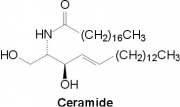

| 16:18, 27 בנובמבר 2017 | Ceramide1.png (קובץ) |  |

23 קילו־בייטים | Motyk | 1 | |